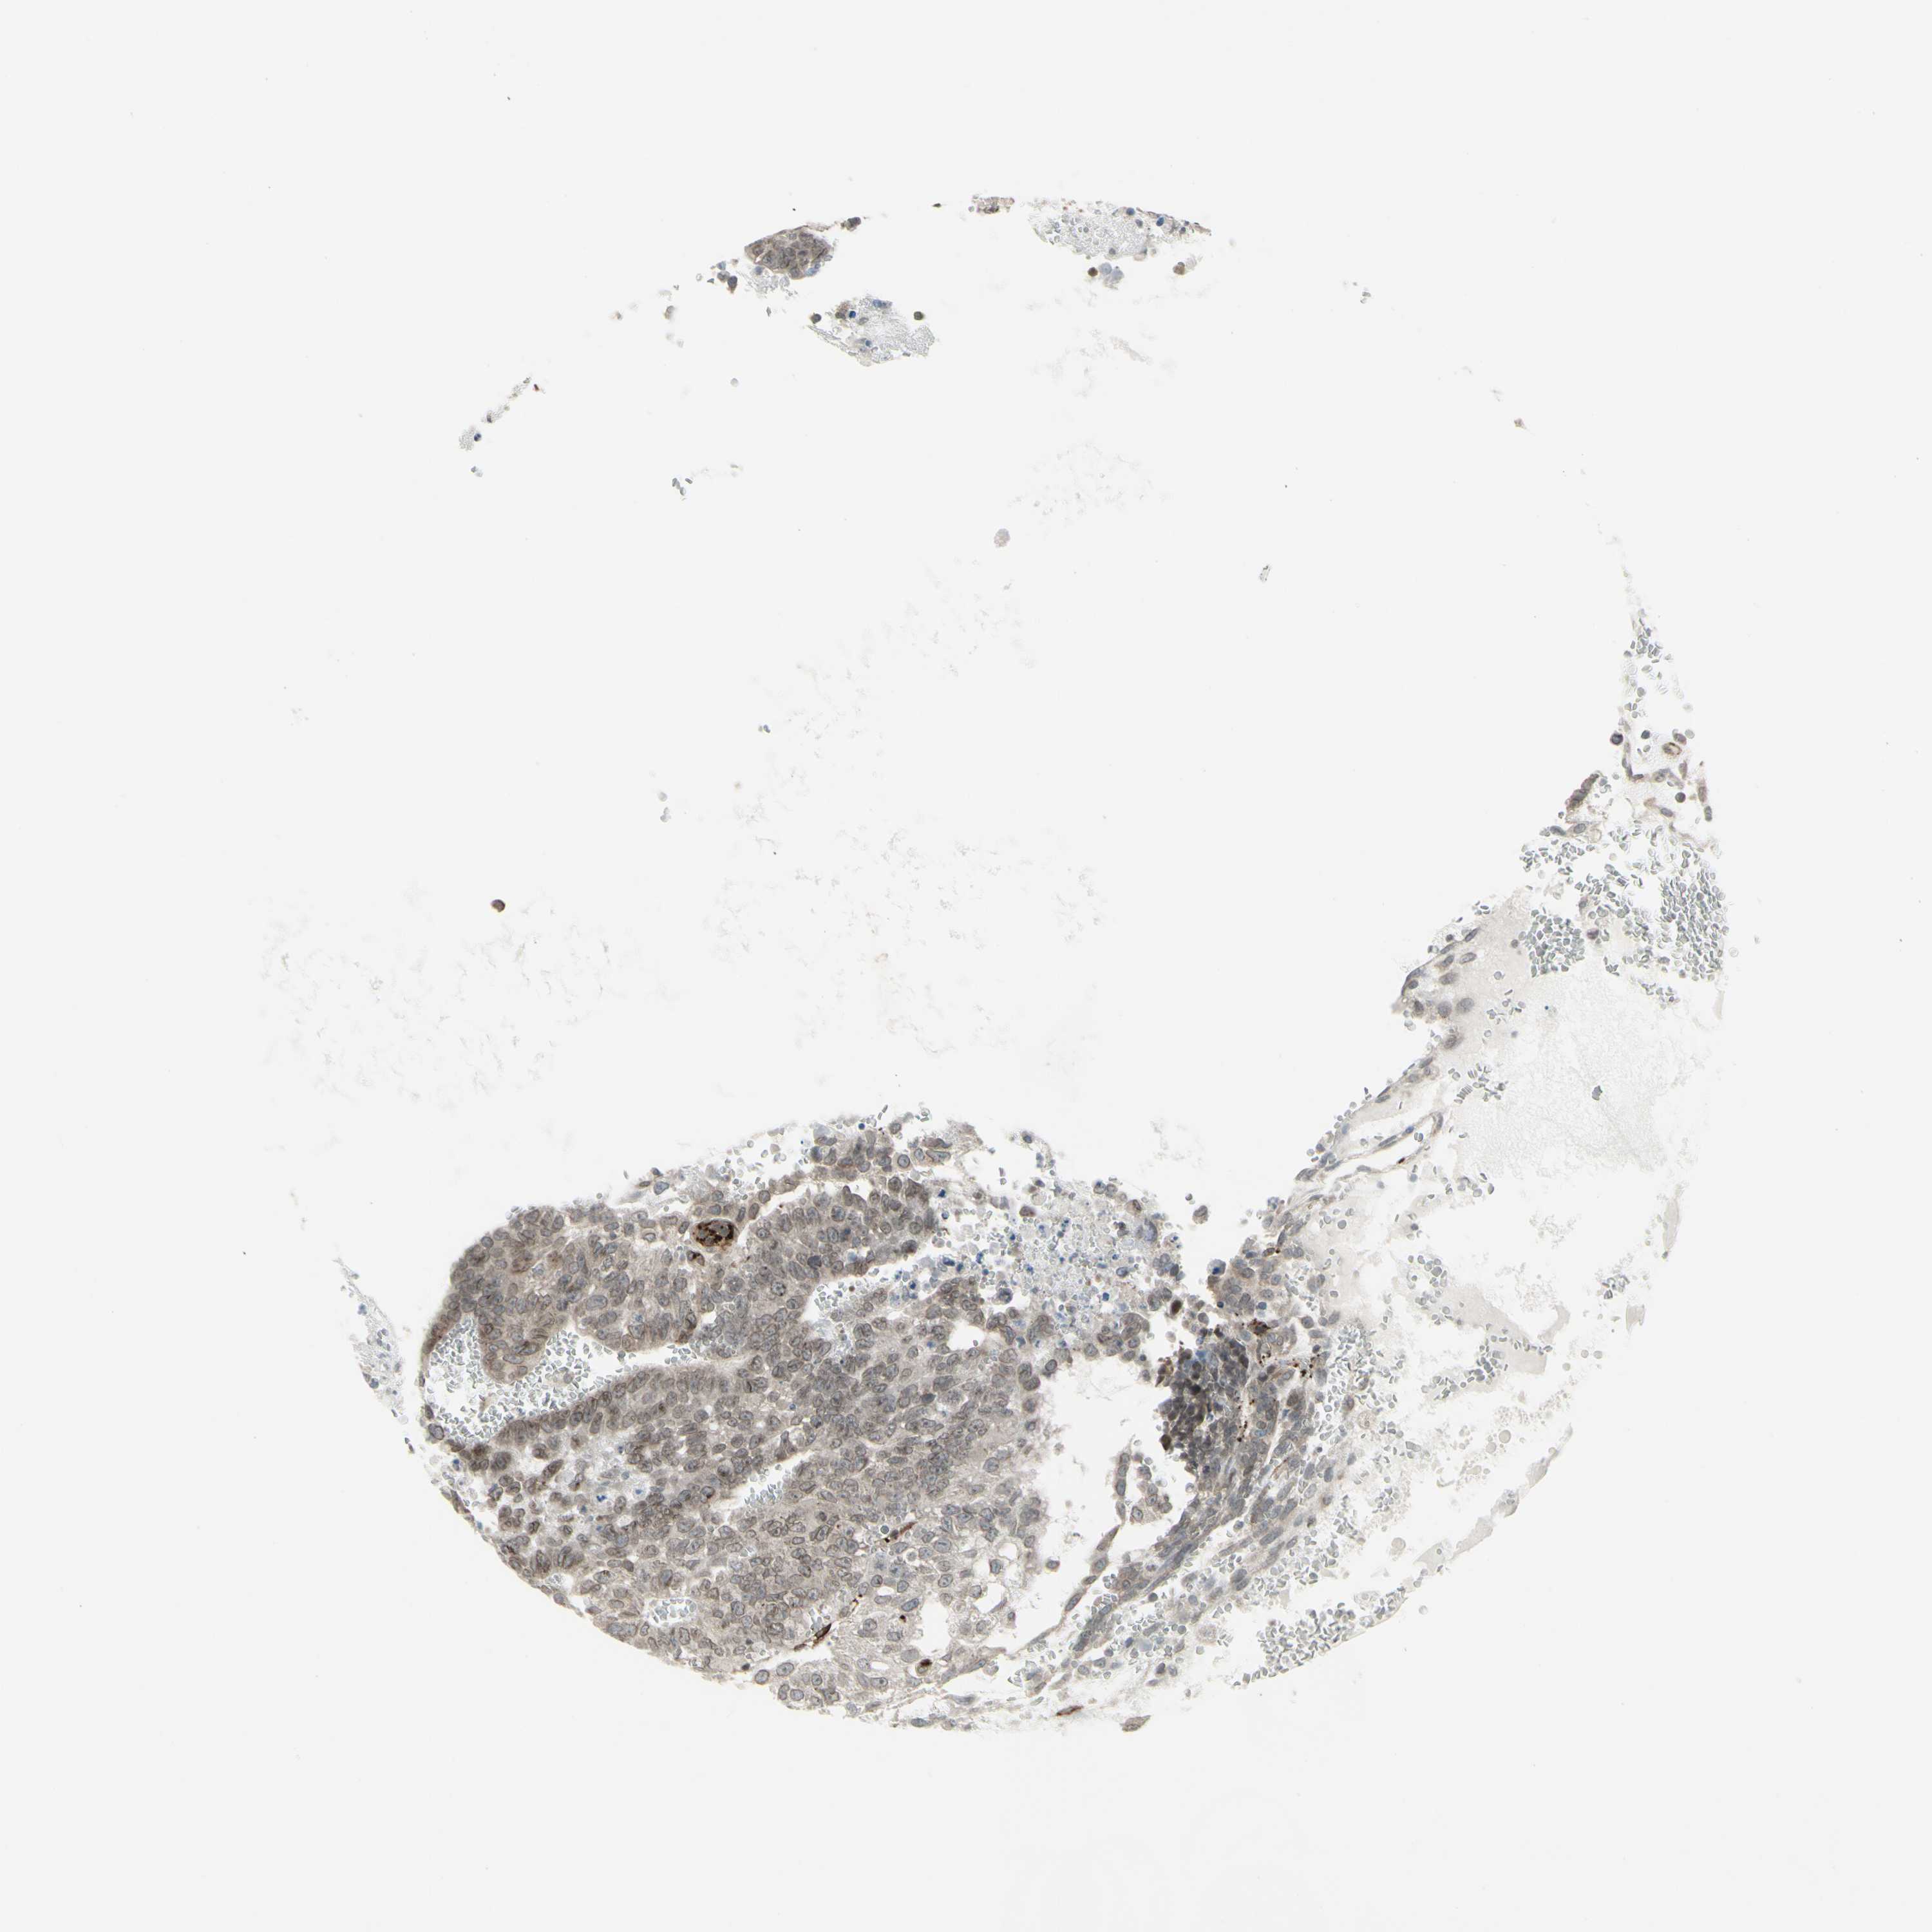

TESTIS CANCER - Protein expressioni

A mouse-over function shows sample information and annotation data. Click on an image to view it in a full screen mode. Samples can be filtered based on level of antibody staining by selecting one or several of the following categories: high, medium, low and not detected. The assay and annotation is described here.

Note that samples used for immunohistochemistry by the Human Protein Atlas do not correspond to samples in the TCGA dataset.

Antibody stainingi

Antibody staining in the annotated cell types in the current human tissue is reported as not detected, low, medium, or high, based on conventional immunohistochemistry profiling in selected tissues. This score is based on the combination of the staining intensity and fraction of stained cells.

Each image is clickable and will lead to virtual microscopy that enables deeper exploration of all samples and also displays staining intensity scores, fraction scores and subcellular localization as well as patient and tissue information for each sample.

Antibody HPA010570

Staining

High

Medium

Low

Not detected

Intensity

Strong

Moderate

Weak

Negative

Quantity

>75%

75%-25%

<25%

None

Location

Nuclear

Cytoplasmic/membranous

Cytoplasmic/membranous,nuclear

Carcinoma, Embryonal, NOS

Seminoma, NOS